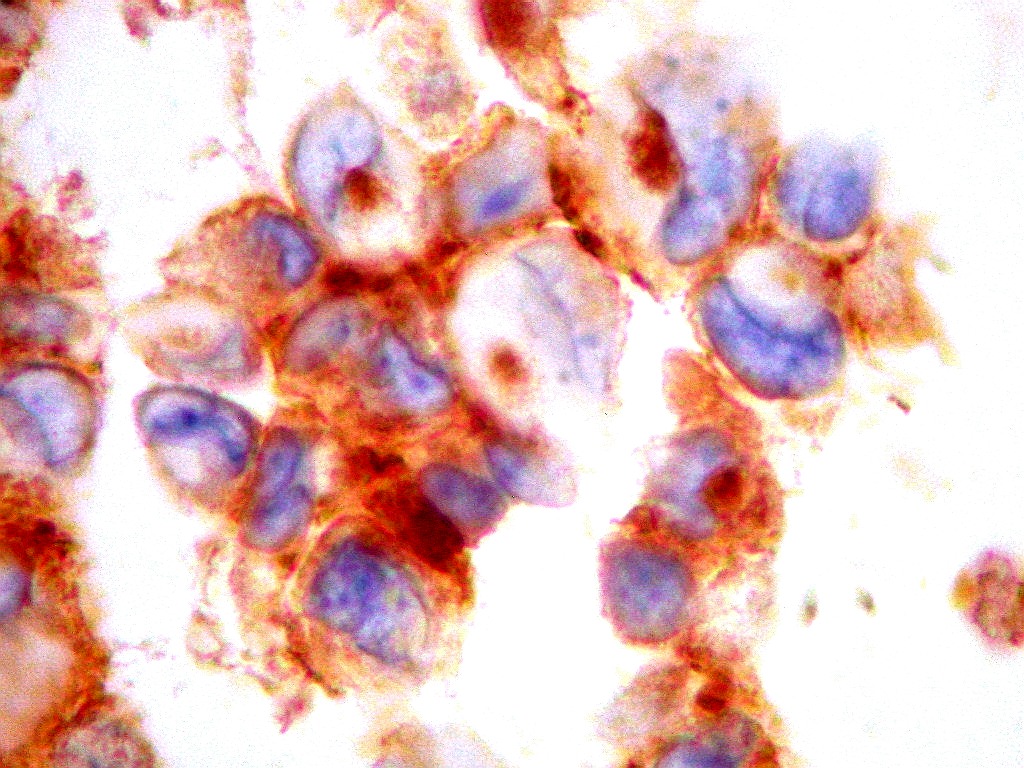

| AE1AE3. Pancitoqueratina, um coquetel para queratinas de alto e baixo peso molecular, indica linhagem epitelial das células neoplásicas. Aqui, fortemente positiva nas células tumorais, com controle interno negativo num folículo linfóide, constituído por linfócitos. Ver marcação para estes em CD3, CD20. Indica diferenciação epitelial. |